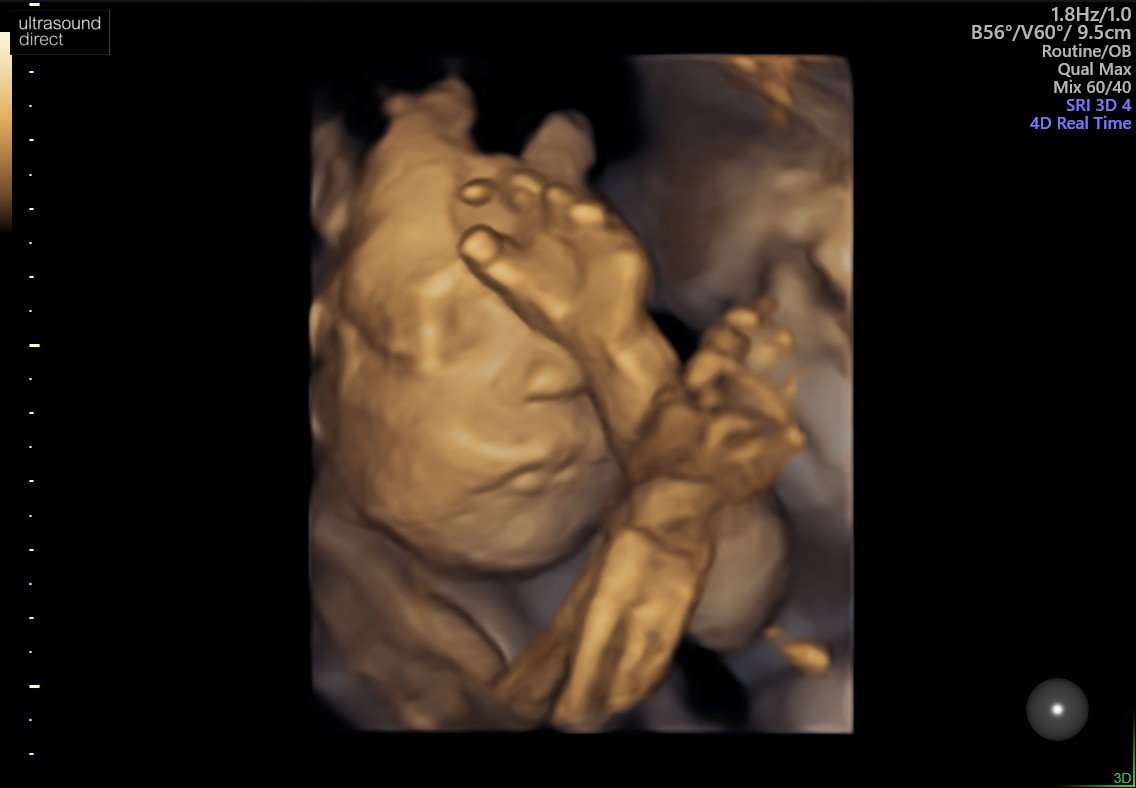

My mielismy USG, z malutka wszystko ok i tak jak of paru dni czuje, jest glowka do dolu. Wiem, ze to jeszcze wczesnie i moze sie obkrecic, ale mam nadzieje, ze tak zostanie.

download%20(7).jpeg